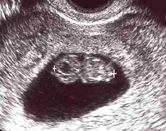

でかっ!?

…といっても、まだ2.7cmの大きさしかないそうです。

でも、2週間前(妊娠7週目)の様子からは考えられないくらいでっかくなっていたので

「これ、この間と同じ縮尺ですか!?」

と慌てて聞いてしまいました。

医者いわく、同じ縮尺らしいんですが…あまりの成長っぷりが、どうも腑に落ちません。

ハハがつわりで苦しんでいる間にキミは…(笑)

今回は、左側の丸い部分は間違いなく頭です。

ほとんど頭やね。

それから、既に、ちっちゃい手足ができていました。

「これがへその緒です」

といって見せてもくれましたが、素人目にはイマイチはっきり分かりません。

まあ、とにかく今のところ順調です。